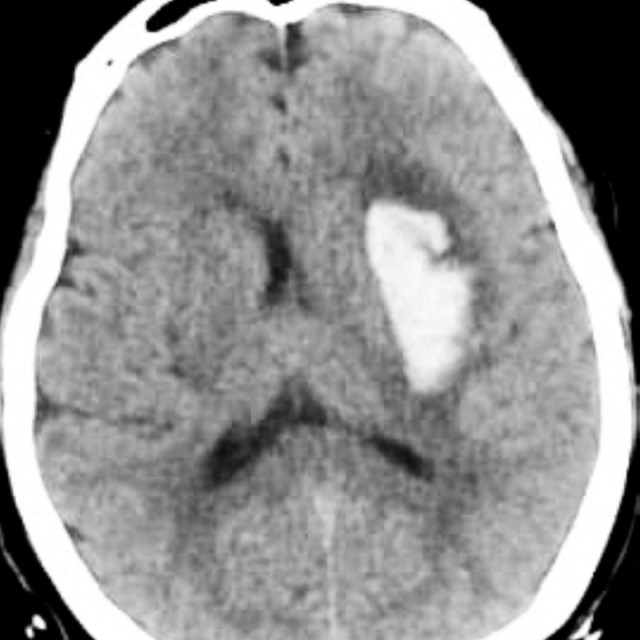

CT snimka.

Rajaaisya/Science Photo Librar